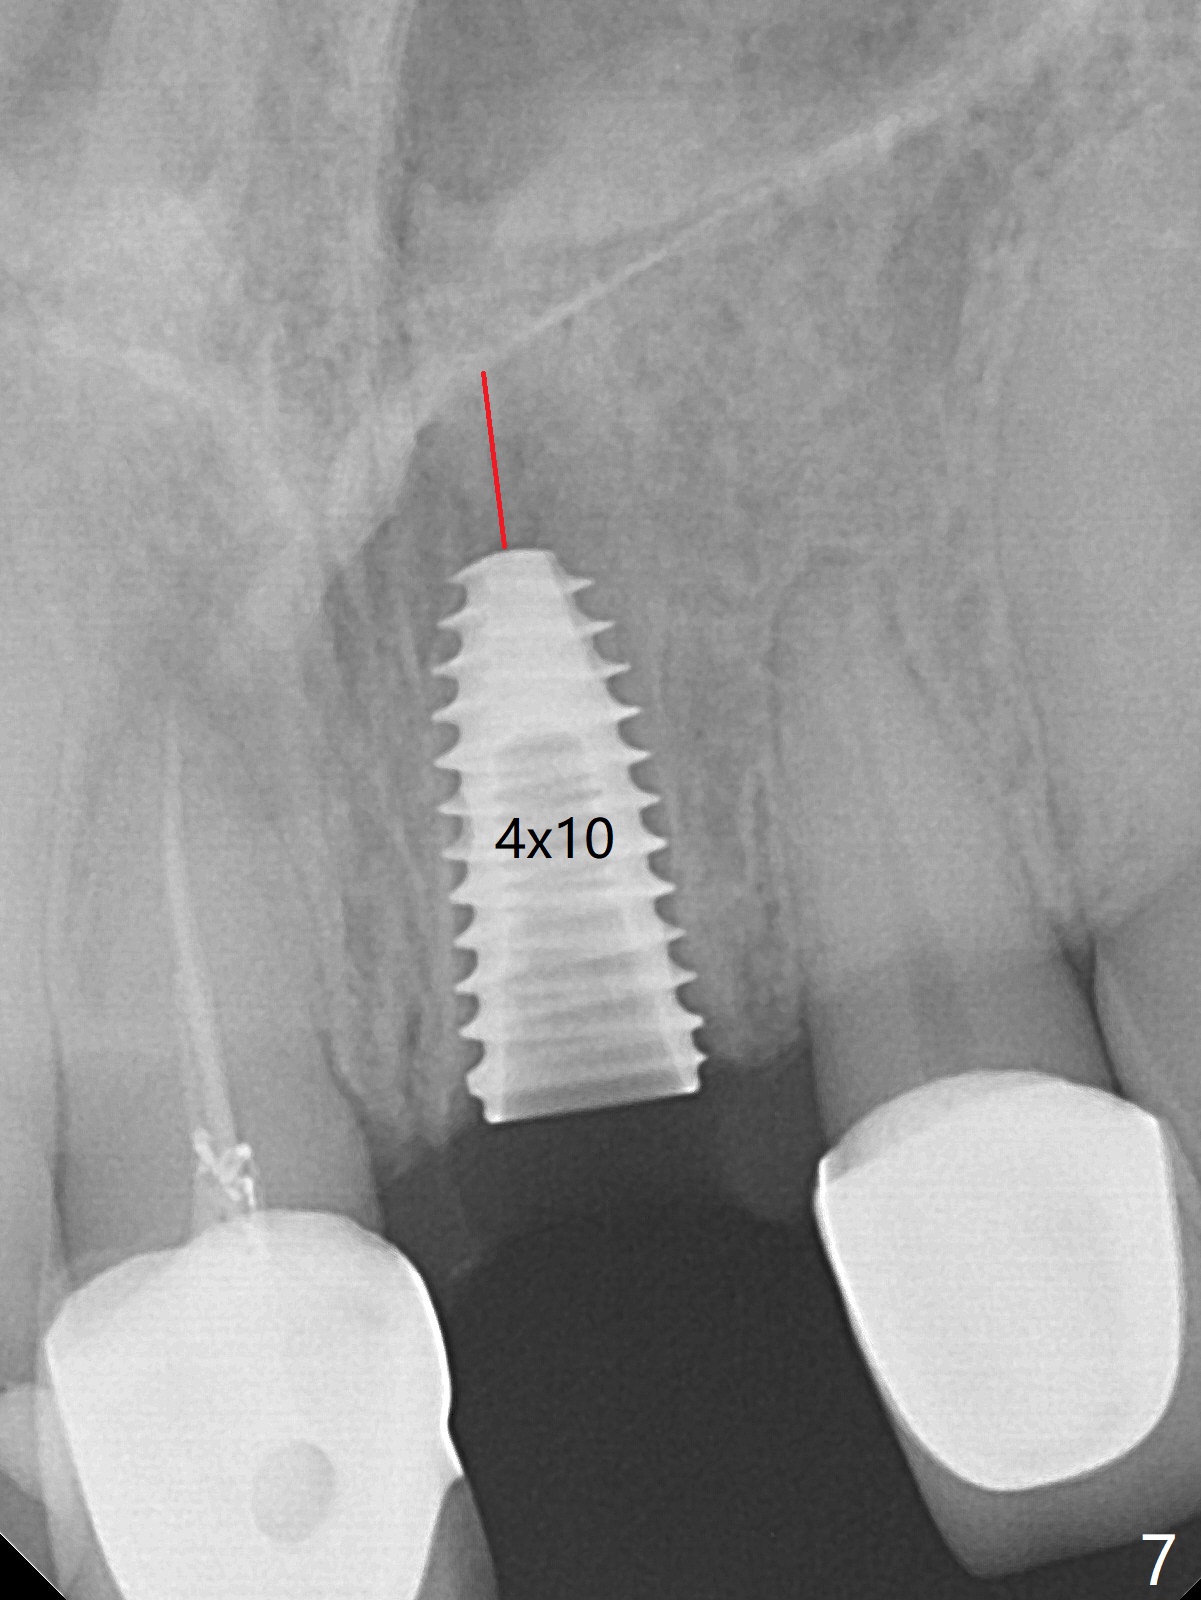

After sectioning the splinted crowns at #8 and 9 (Fig.1,2 (*: open bite)), the tooth #9 is deemed nonsalvageable because of caries and the crown/retainer of #8 is recemented. The trajectory of initial osteotomy is off (Fig.3 (red line: ideal trajectory)). Using Lindamann bur twice does not improve the trajectory (Fig.4,5). It appears that a new osteotomy should be established in the distal wall of the socket (Fig.5 red line (initial entry point and angle), Fig.6). Following sequential osteotomy, a 4x10 mm dummy implant is placed with stability and ~ 3.5 mm apical space (Fig.7 red line). A final implant (4x11.5 mm) is placed subcrestal (except buccal, Fig.8). With further placement of the implant, a 4.5x5.5(3) mm abutment and Vera graft are placed (Fig.9) prior to fabrication of an immediate provisional. In all, a new osteotomy site should be set up when the trajectory is to be changed substantially. There is no gross bone loss 4.5 months postop (Fig.10). There is shade mismatch when a porcelain-fused-Zirconia crown is tried in (Fig.11, as compared to Fig.1). The latter is corrected when a PFM crown is cemented (Fig.12).